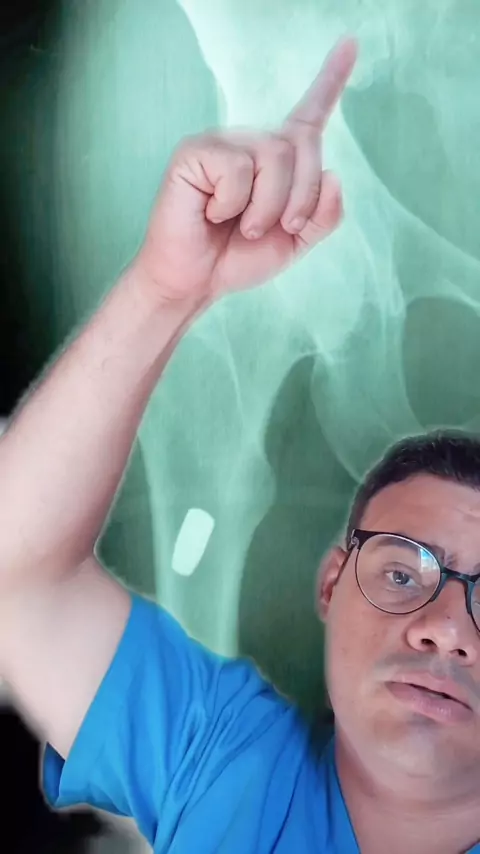

radiografia de coxofemoral com projetil de arm de fogo. #estreladocarnavalkwai #radiology #medicia